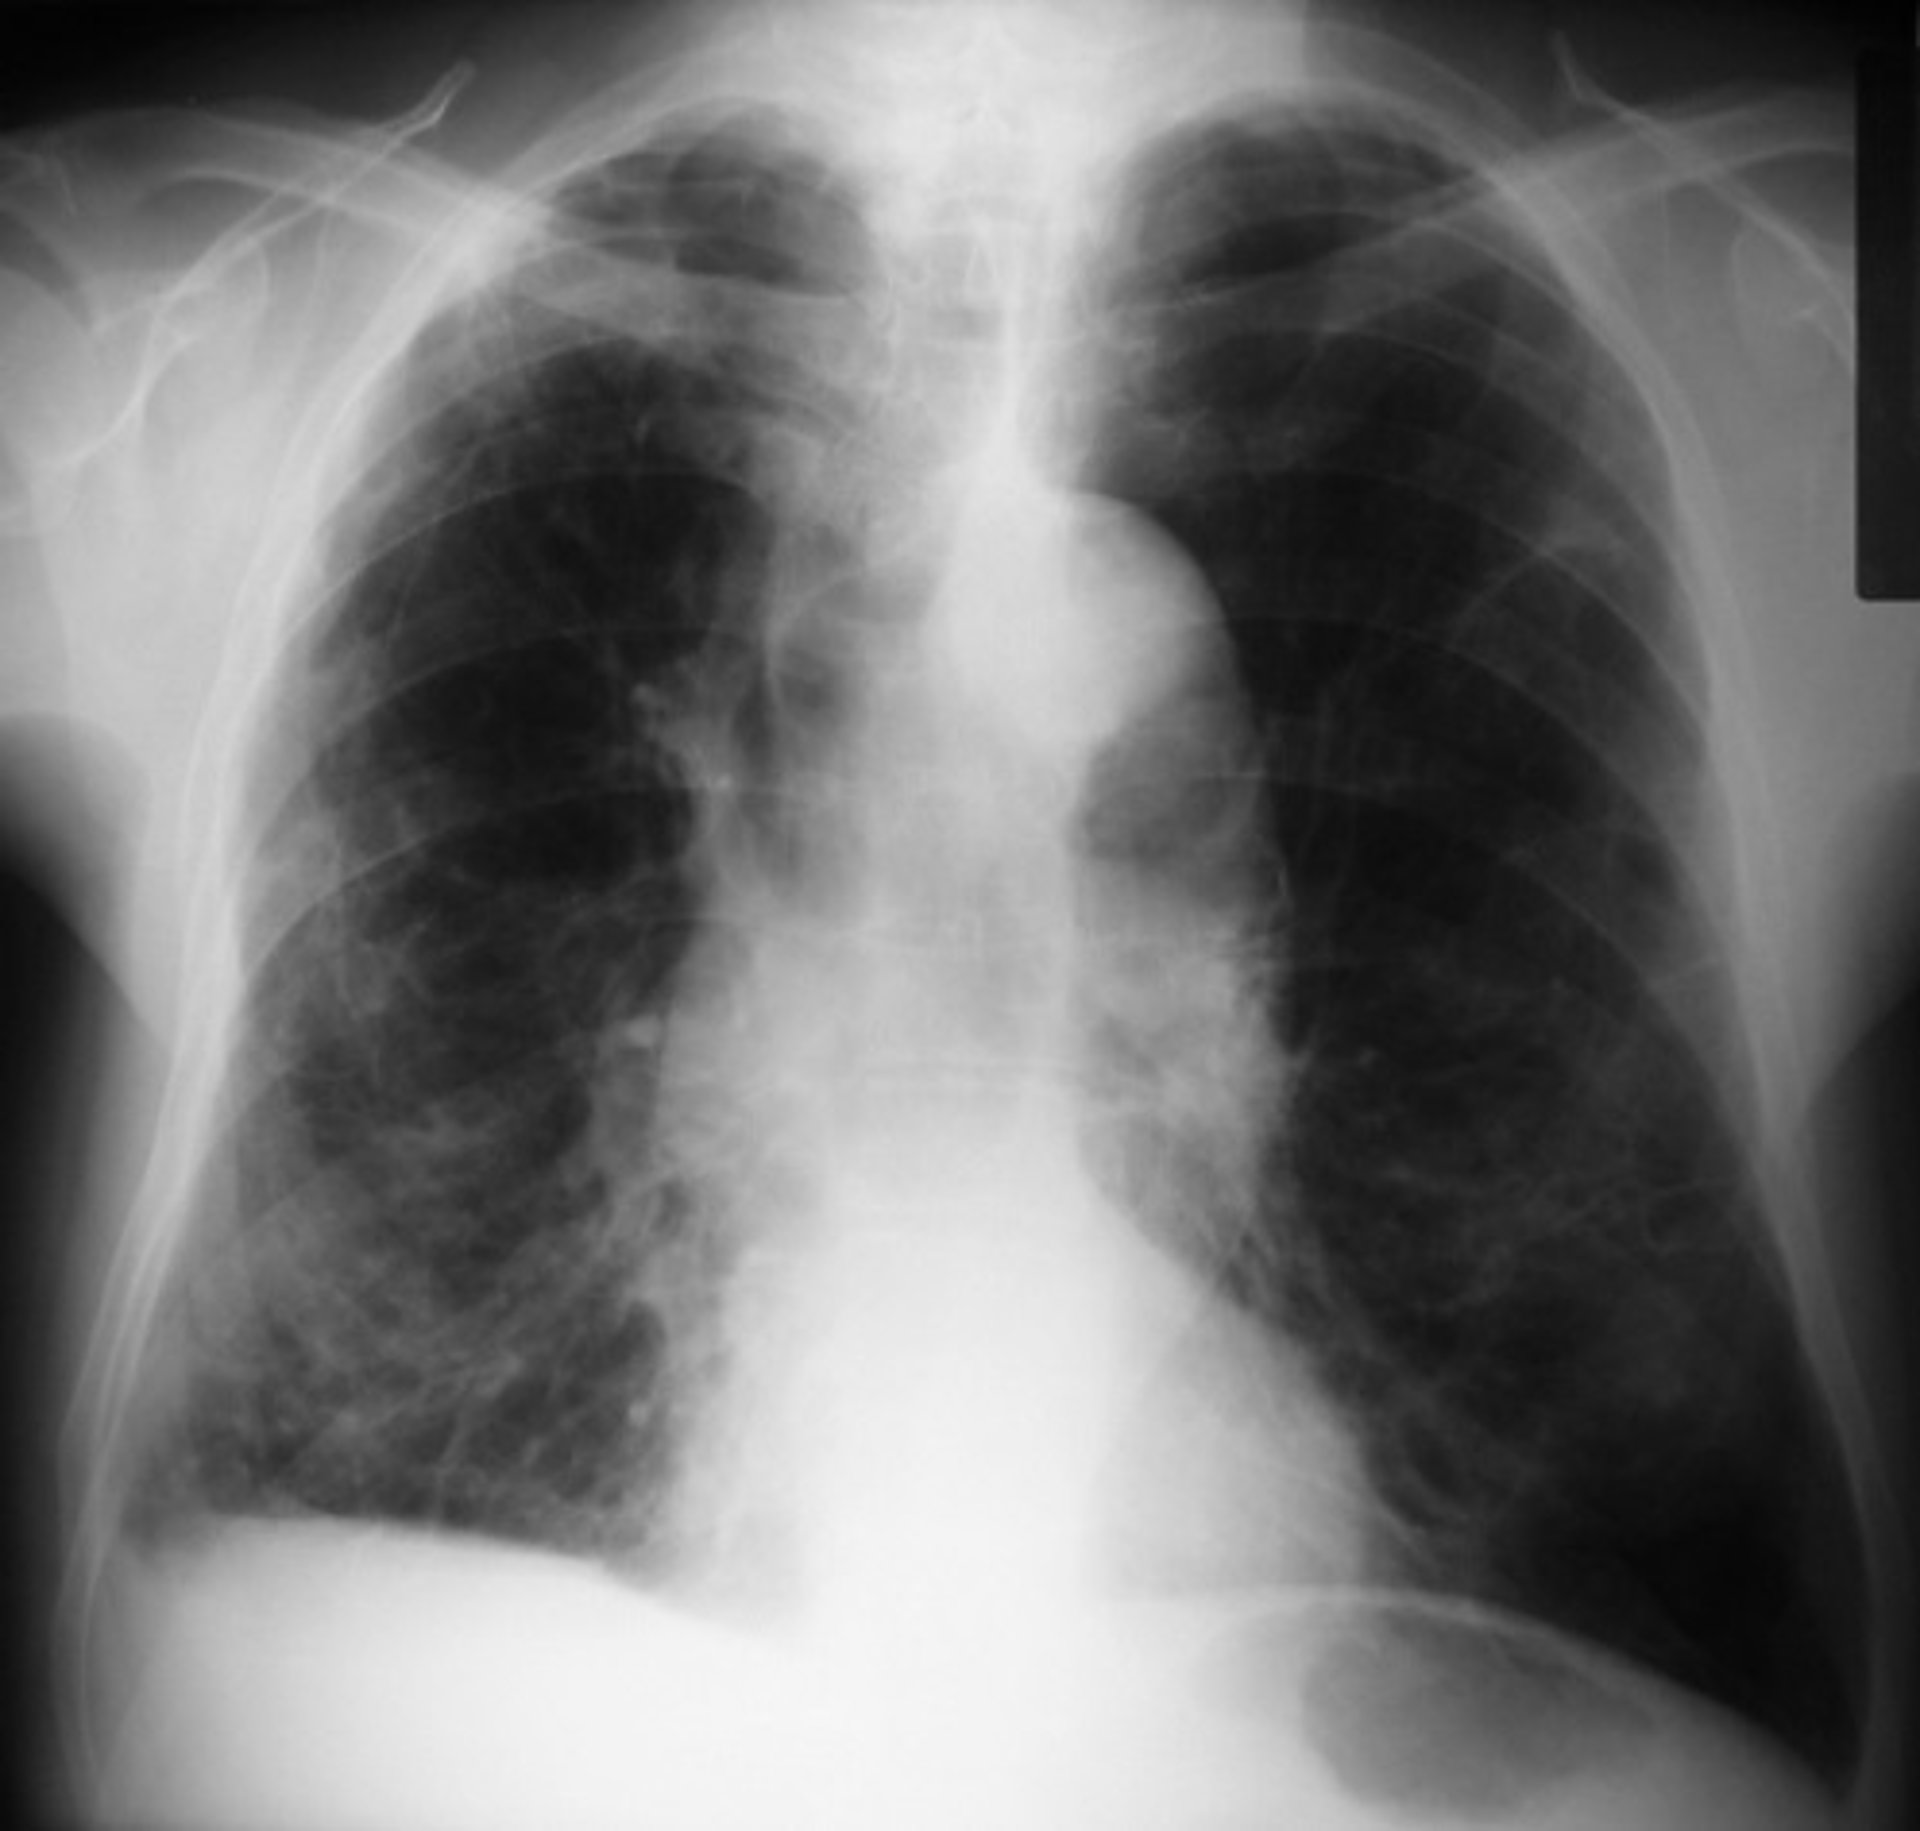

EPOC - FLICKR//PICASA - Archivo